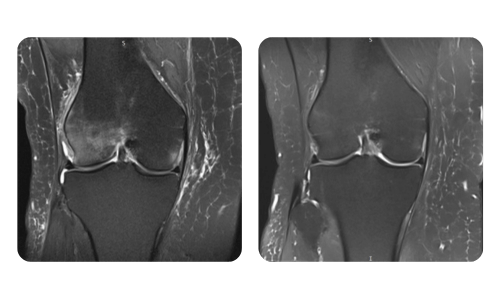

The progress of our patients, measured before and after hyperbaric therapy, reflects the efficiency and positive impact of the treatment. Discover documented results of hyperbaric therapy at Hyperbarium Oradea clinic, based on clinical evaluations and objective data that highlight significant improvements in various conditions.